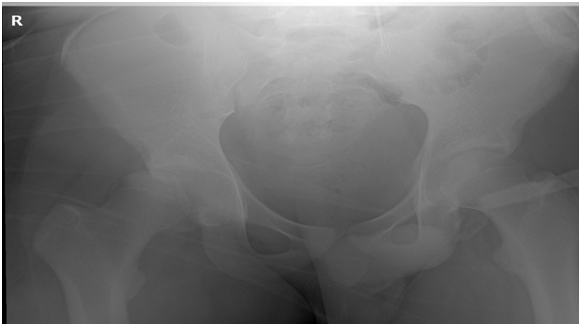

X ray

Fracture dislocation right hip -pip kin type 2

Figure 1 Neglected fracture dislocation hip 1.